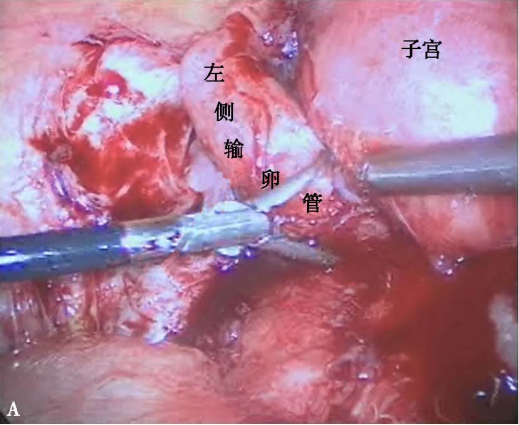

输卵管粘连梗阻

A左侧输卵管迂曲、水肿,明显增粗,输卵管伞端消失;B左侧输卵管与周围组织广泛粘连,导致输卵管梗阻